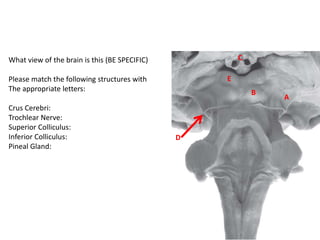

What view of the brain is this (BE SPECIFIC)

Please match the following structures with

The appropriate letters:

Crus Cerebri:

Trochlear Nerve:

Superior Colliculus:

Inferior Colliculus:

Pineal Gland:

C

B

E

A

D